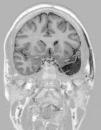

Para ello presentamos dos casos de pacientes mujeres de 50 y 42 años con crisis desde la infancia y diagnosticadas de esclerosis temporal mesial. Ambas fueron intervenidas por nosotros en el año 2000 mediante amigdalohipocampectomía con resección parcial amigdalar más lobectomía temporal izquierda y derecha respectivamente. Las dos pacientes no presentaron nuevas crisis parciales complejas durante los primeros 6 años, empeorando posteriormente por lo que fueron reintervenidas para monitorización con electrodos subdurales y profundos. En ambas se evidenció un inicio ictal compatible con el electrodo situado en la amígdala. La subsiguiente resección del tejido donde se situó el electrodo amigdalar dejó a las dos pacientes libres de crisis.

Two patients are presented who were 50 and 42 years old at the time of surgery. They suffered from seizures since childhood and were diagnosed with mesial temporal sclerosis. A temporal lobectomy with hippocampectomy and partial amygdalectomy was performed on both patients in the year 2000, with one patient operated on the right side and the other one on the left side. Both patients were seizure free after surgery for 6 years, but presented again with seizures after that time. They were evaluated again for surgery, and subdural grids were placed, together with a deep electrode in the remnants of the amygdala. The amygdalar electrode showed to be the seizure onset in the two cases, and its resection rendered both patients seizure free.